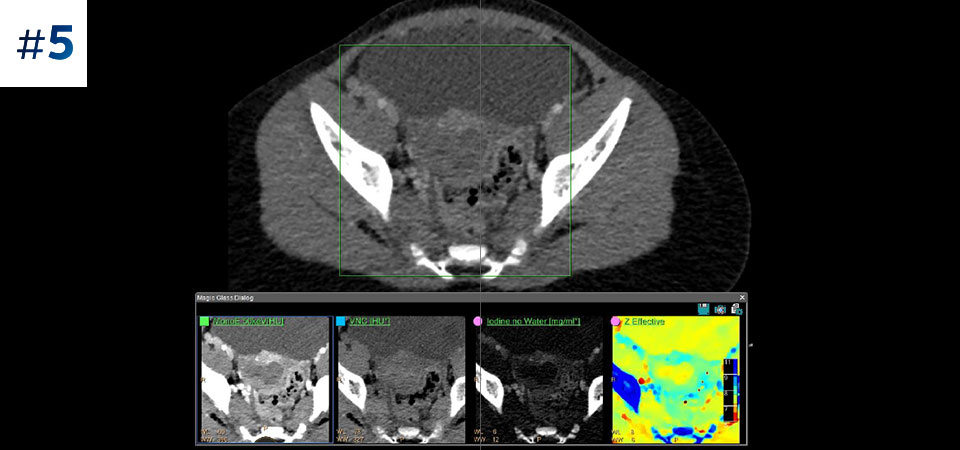

With detector-based spectral, you acquire multiple layers of data—conventional and spectral—within a single exposure and without special scan modes for improved tissue characterization and visualization.

Scan as usual A single scan for fast, low-dose conventional and spectral data for every patient, every time.

Always available 100% spectral, 100% of the time for results that are always available on-demand, even retrospectively.

Reduced follow-up exams Improved tissue characterization and visualization may reduce the need for follow-up scanning for sub-optimal exams and incidental findings.

Across patient types Benefits a wide range of patient types from pediatric to bariatric.